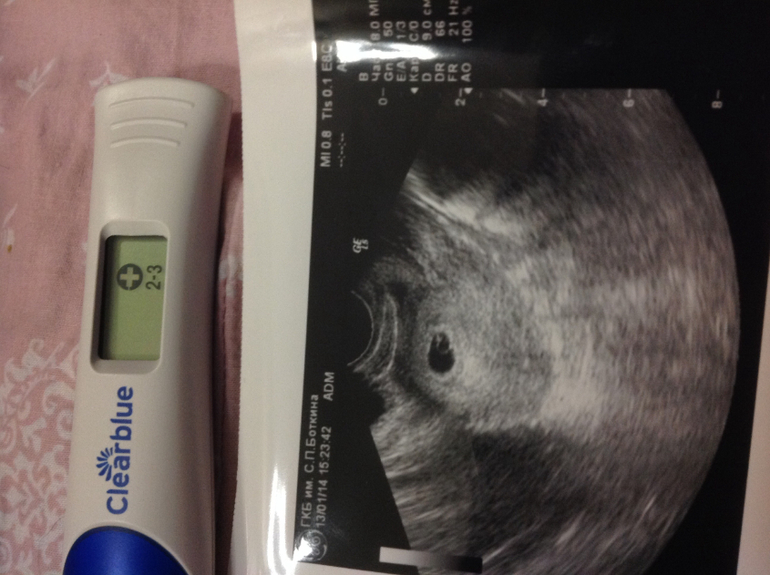

И так нам уже 4-5 недель !!меня ус покоили что пока ничего не слышно так как маленький срок,через неделю уже будет все стучать))сказали что тонуса матки нет,что все хорошо)теперь я спокойный удав)оказывается что это все поздняя овулька ,поэтому не стоит переживать!)сказали сдать кровь с утра чтоб все было в норме )и можно уже на учет вставать,но пока не буду спешить где-нибудь в феврале встану когда уже скрининг надо будет делать!!) девочки скажите на что самое главное надо обратить внимание в первом триместре??)